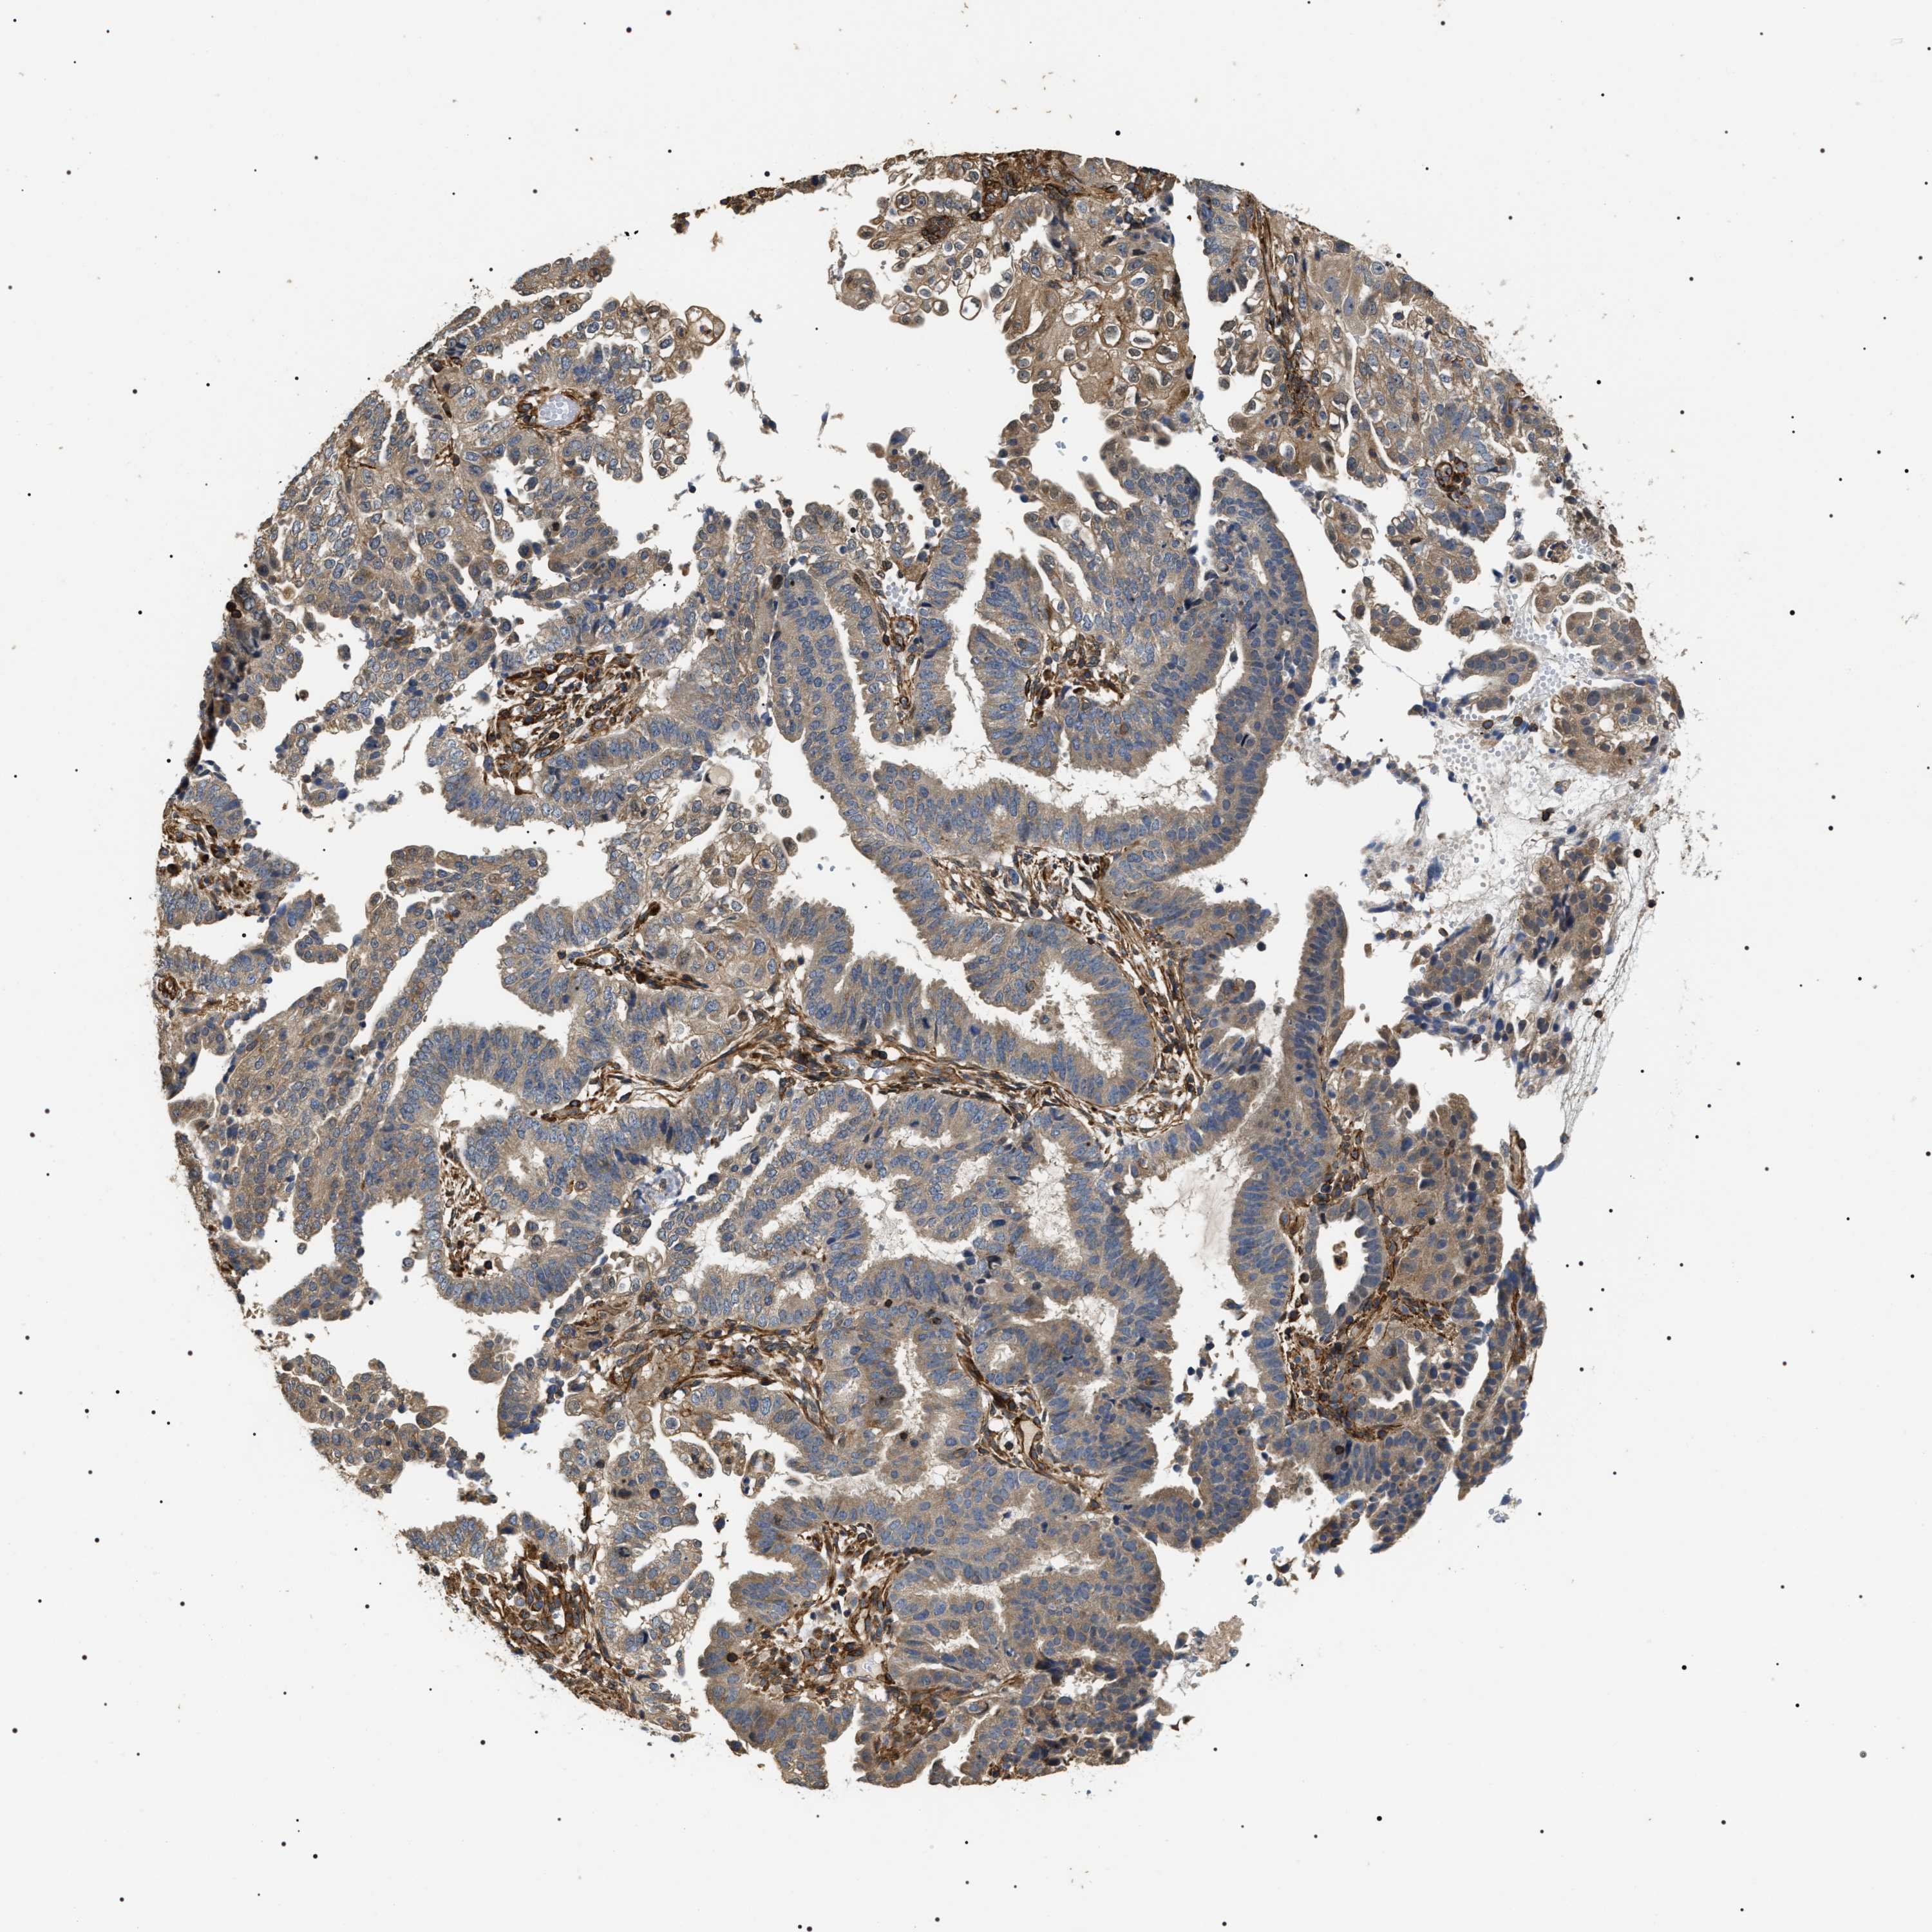

ENDOMETRIAL CANCER - Protein expressioni

A mouse-over function shows sample information and annotation data. Click on an image to view it in a full screen mode. Samples can be filtered based on level of antibody staining by selecting one or several of the following categories: high, medium, low and not detected. The assay and annotation is described here.

Note that samples used for immunohistochemistry by the Human Protein Atlas do not correspond to samples in the TCGA dataset.

Antibody stainingi

Antibody staining in the annotated cell types in the current human tissue is reported as not detected, low, medium, or high, based on conventional immunohistochemistry profiling in selected tissues. This score is based on the combination of the staining intensity and fraction of stained cells.

Each image is clickable and will lead to virtual microscopy that enables deeper exploration of all samples and also displays staining intensity scores, fraction scores and subcellular localization as well as patient and tissue information for each sample.

Antibody HPA020386

Staining

High

Medium

Low

Not detected

Intensity

Strong

Moderate

Weak

Negative

Quantity

>75%

75%-25%

<25%

None

Location

Nuclear

Cytoplasmic/membranous

Cytoplasmic/membranous,nuclear

Adenocarcinoma, NOS

Adenoma, NOS